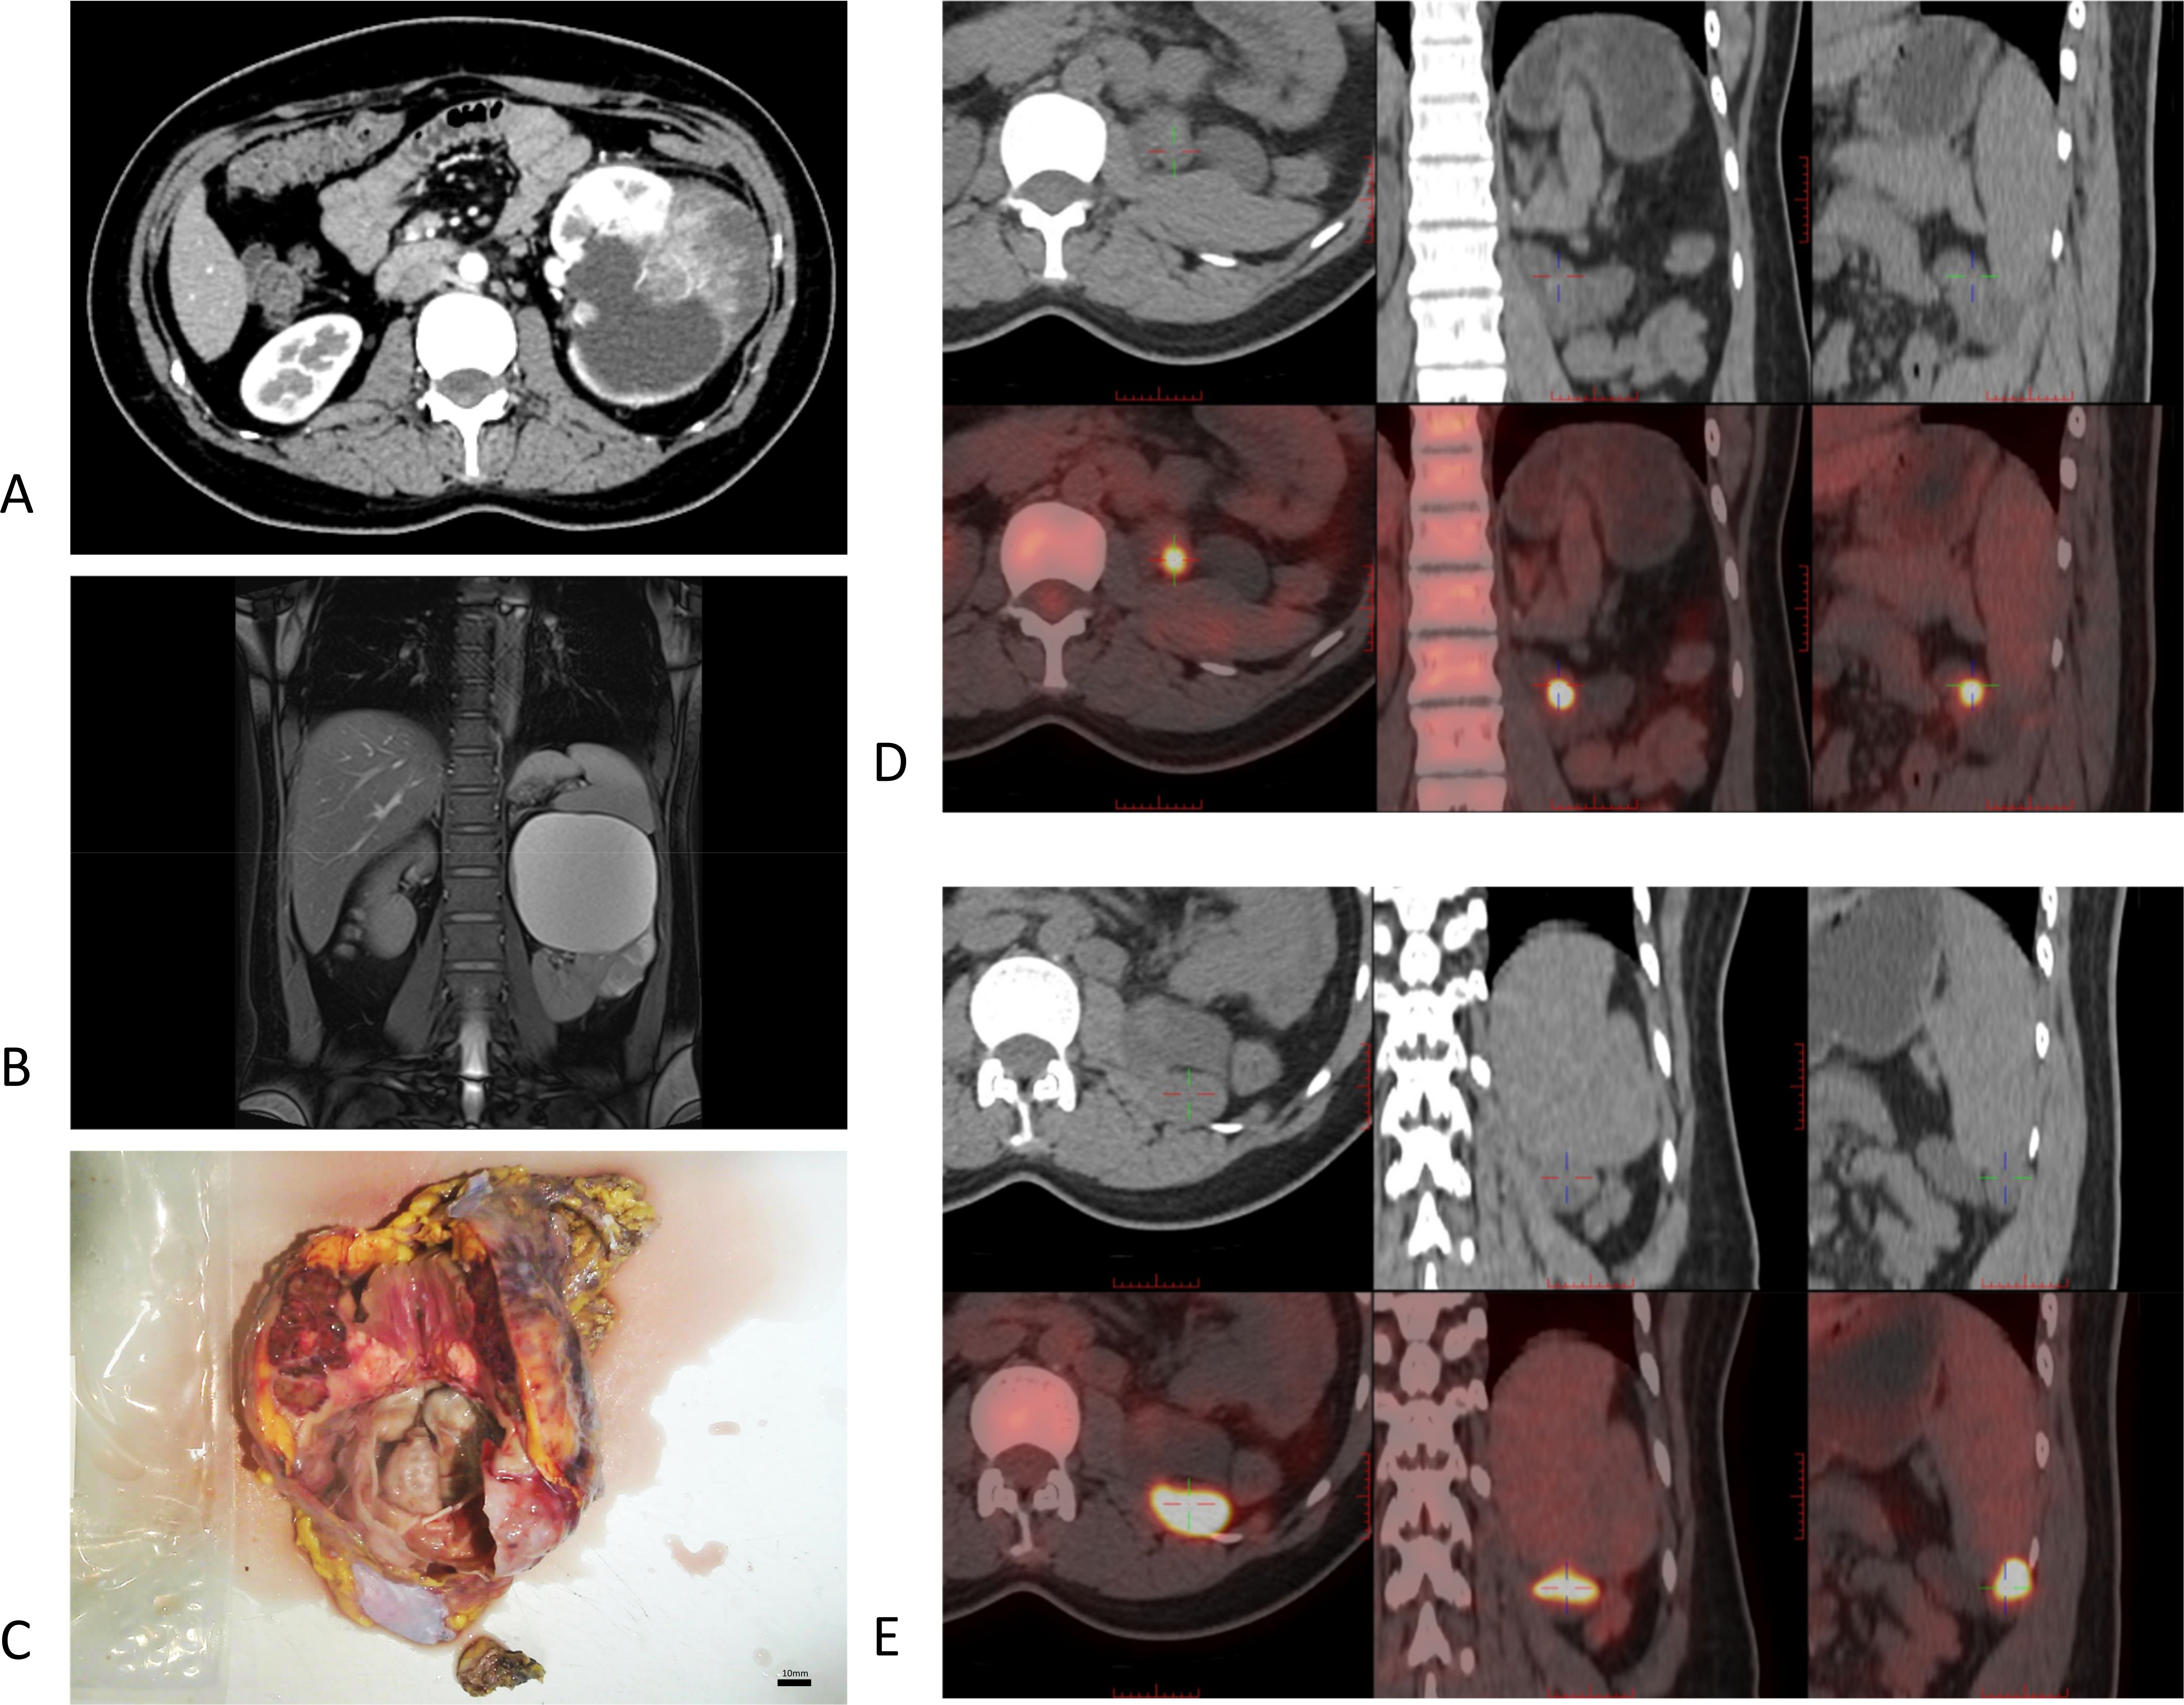

Figure 1

Figure 1. Imaging findings for Cases 1–4 [(A), Case 1; (B) and C. Case 2; (D, E), Case 3; F, Case 4]. (A) In Case 1, no enhancement was observed in the cystic region post-contrast. MPR view as shown, with arrows indicating the location of the suspected solid mass. (B, C) Case 2 demonstrates a T1- and T2-hyperintense mass in the left adrenal region, suggestive of adrenal metastasis. Renal artery CTA reveals no significant enhancement around the cystic lesion with sparse vascularity. (D, E) Case 3: A slightly hyperdense nodule with diminished enhancement in both parenchymal and delayed phases. Contrast-enhanced ultrasound imaging: The lesion demonstrated near-parenchymal enhancement in the early phase, with slow resolution in the late phase, appearing slightly hypointense. (F) Case 4: Non-contrast CT shows a well-defined tumor margin with a cystic–solid mixture. Contrast enhancement exhibits rapid uptake and washout, revealing punctate calcifications and patchy areas of increased density within the lesion.

As a common screening tool, ultrasound examination effectively detected the presence of mixed cystic–solid lesions (Figure 1E). CT scan: The tumors were characterized by well-defined borders with mixed cystic and solid components. The cystic regions demonstrated a lack of enhancement post-contrast, whereas the irregular cyst walls and solid components showed heterogeneous enhancement that was typically mild and progressive. These imaging features are consistent with the findings previously reported by Fu et al. and Sandro (Figures 1A, F, 2A) (6, 7).

Some patients’ tumors exhibited rapid contrast enhancement and subsequent washout (Figure 1F), a phenomenon that has been previously documented (2). Renal artery computed tomography angiography (CTA) revealed minimal enhancement around the cystic lesions, with an overall sparse vascular distribution (Figure 1C). MRI demonstrated a pattern of heterogeneous mixed signals. T1-weighted imaging (T1WI) showed isointense to hypointense areas, while T2-weighted imaging (T2WI) revealed isointense to hyperintense signals. The renal medulla was not prominent and demonstrated a non-uniform enhancement pattern following contrast administration. In Case 2, combined imaging findings strongly suggested a renal tumor with adrenal metastasis, as evidenced by slightly prolonged T1 and T2 signals in the left adrenal region (Figure 1B). In Case 5, the MRI scan further characterized the complex nature of the tumor, which presented as a giant upper pole cyst with a distinct solid mass in the middle and lower portions (Figure 2). On MRI, the solid component exhibited slightly hypointense signals on T1WI and hyperintense signals on T2WI, with a heterogeneous internal signal pattern. Significant cortical enhancement was noted during T1-weighted contrast-enhanced scanning, which was suggestive of intratumoral hemorrhage.